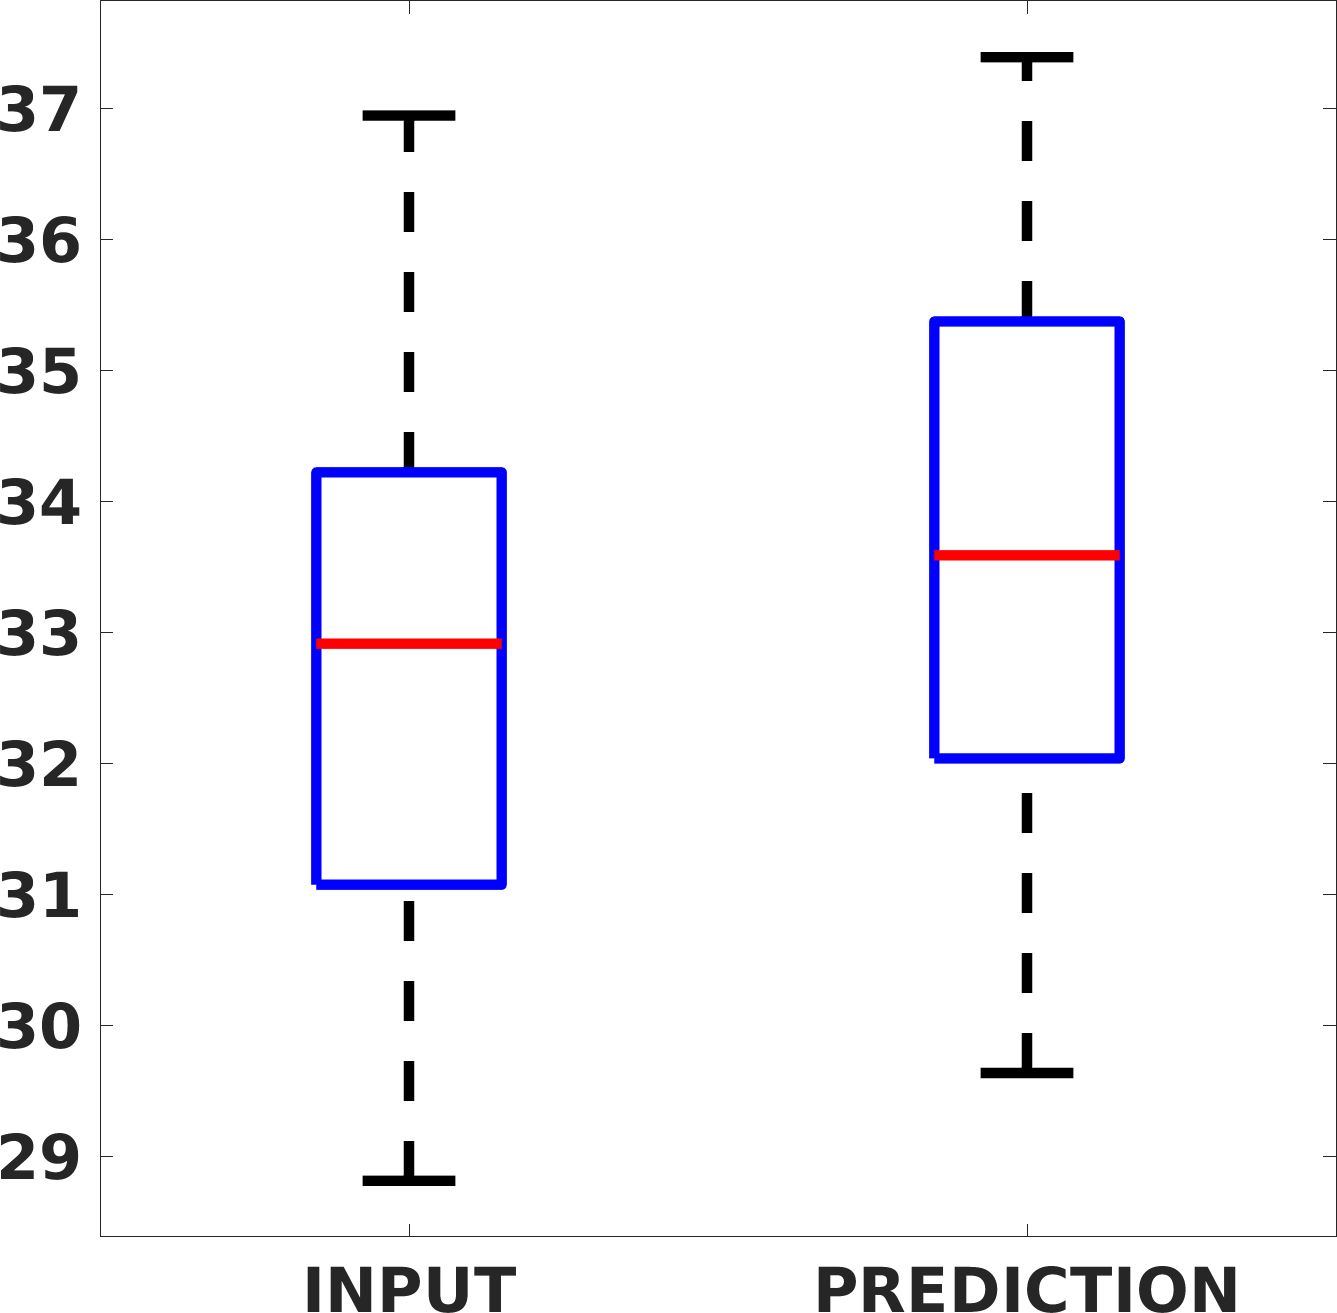

Fig. 7(a-b-c, left) shows the box plot of the statistics of the PSNR on three different anatomical districts, comparing the target images with the prediction and the cubic convolution, respectively. The metrics are computed on a data set of 200 images of the same district and with the same up-sampling factor. We report that the PSNR median value improves of on obstetric 2X raw images, on cardiac 2X raw images, and on abdominal raw 4X images.

Fig. 8 shows the box plot of the SSIM (a-b-c, left) and MAE (a-b-c, right) quantitative metrics, as performed for PSNR metric. Also, these metrics show that our method improves the results of Cubic convolution both in terms of average value and variability. For example, the SSIM median value improves of on obstetric 4X images and the MAE median value improves of on cardiac 2X images.

Fig. 17 (left) shows the box plot of the quantitative metrics, comparing the target images with the prediction and the Cubic convolution, respectively. The PSNR metric is computed on a data set of 200 images, belonging to the same district, and with the same up-sampling factor. Analysing the obstetric anatomical district and concerning the corresponding raw images (Fig. 7 (a, left)), the denoising allows the network to significantly improve the results of the up-sampling and the prediction. In particular, comparing the target images with the predicted images, the median PSNR value of obstetric 2X denoised images is 51.8, compared to the median PSNR value of obstetric 2X raw images which is 36.9.